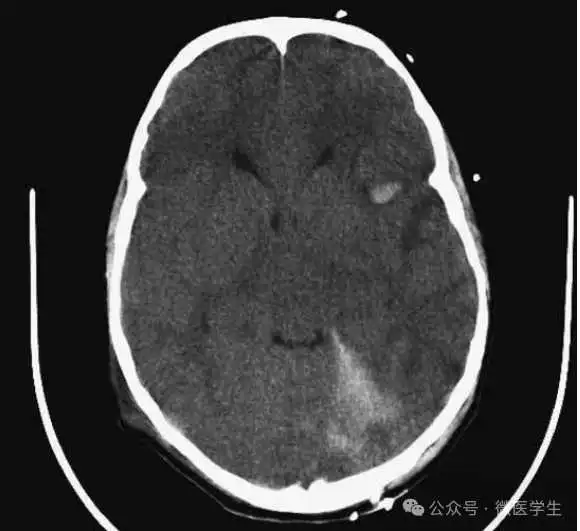

高血压性脑出血:

- 自发性出血;

- 继发于长期高血压及慢性血管病;

- 常见于基底节区、丘脑、脑桥、小脑。

A:占位效应,相邻脑沟、脑池消失;

F:脑出血破入四脑室。

▲

钩回疝:

是当代偿机制不能适应占位性病变时的结果。

基底节区大量高血压性脑出血,破入脑室及蛛网膜下腔,周围水肿,脑干周围空间消失;脑干出血、脑积水。